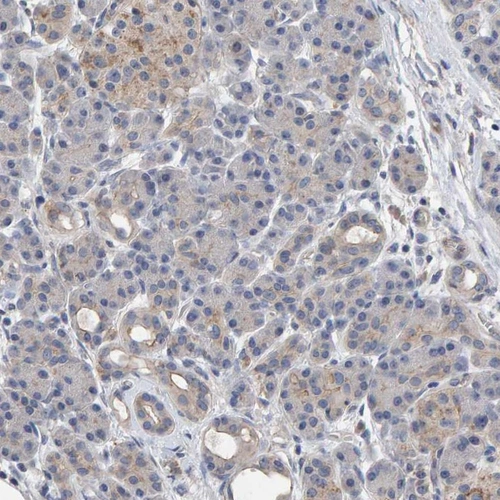

Immunohistochemistry analysis in human cerebral cortex and pancreas tissues using Anti-EFR3A antibody. Corresponding EFR3A RNA-seq data are presented for the same tissues.